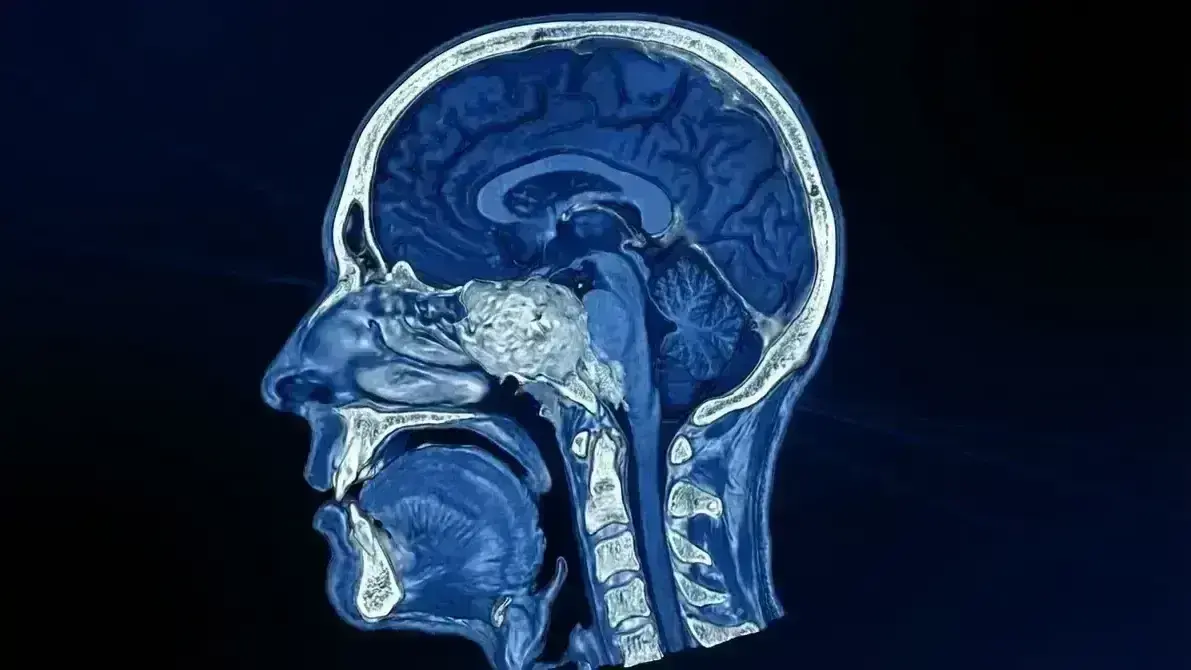

Cirurgia para remover um cordoma, tumor raro que nasce nas vértebras ou na base do crânio (clivus — osso na parte central da cabeça, atrás da nasofaringe). Este tumor cresce lentamente, mas pode comprimir o tronco encefálico, nervos cranianos e estruturas vitais, causando sintomas graves.

1️⃣ Planejamento: Imagem detalhada (RM e TC) para mapear relação com artérias vertebrais e tronco encefálico.

3️⃣ Exposição: Acesso ao clivus, identificação cuidadosa do tumor e estruturas vitais adjacentes (tronco, nervos, vasos).

4️⃣ Ressecção: Remoção cuidadosa do tumor em peças ou fragmentos, preservando o máximo de tecido sadio.